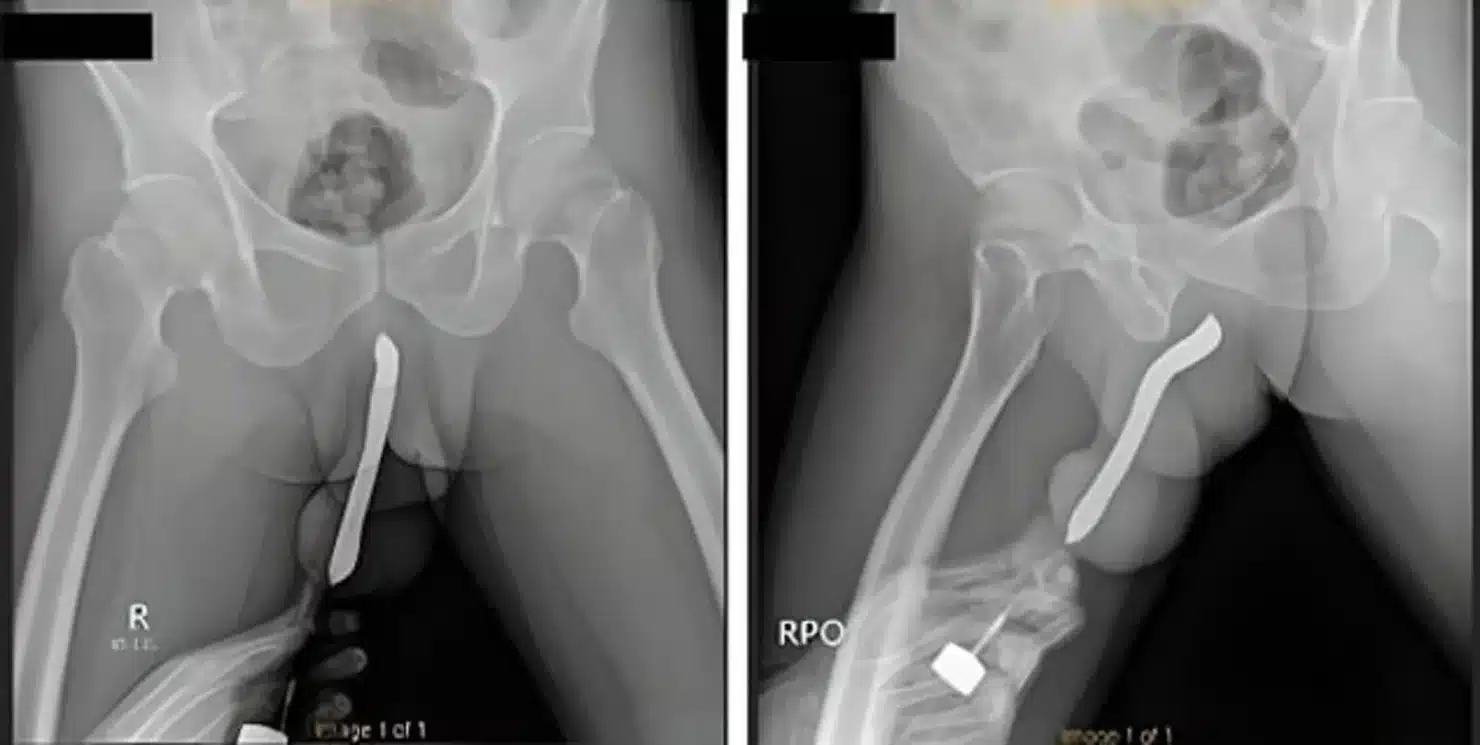

รายงานระบุว่า ไม่กี่วันที่ผ่านมา ชายคนนี้มีเพศสัมพันธ์กับผู้หญิง โดยใช้ท่า “ผู้หญิงอยู่บน ผู้ชายอยู่ล่าง” ผลปรากฏว่า อวัยวะเพศของเขาหัก ไม่เพียงเท่านั้น ยังผิดรูปอีกด้วย ชายคนนี้ต้องทนทุกข์ทรมานนานถึง 12 ชั่วโมง กว่าจะไปพบแพทย์ได้

แพทย์ระบุว่า อวัยวะเพศของเขาหัก ทำให้เกิดอาการคั่งเลือดและบวม แพทย์จึงผ่าตัดนำแปรงสีฟันออก แล้วซ่อมแซมอวัยวะเพศ การผ่าตัดใช้เวลาประมาณ 2 ชั่วโมง เขาต้องนอนพักรักษาตัวในโรงพยาบาล 3 วัน